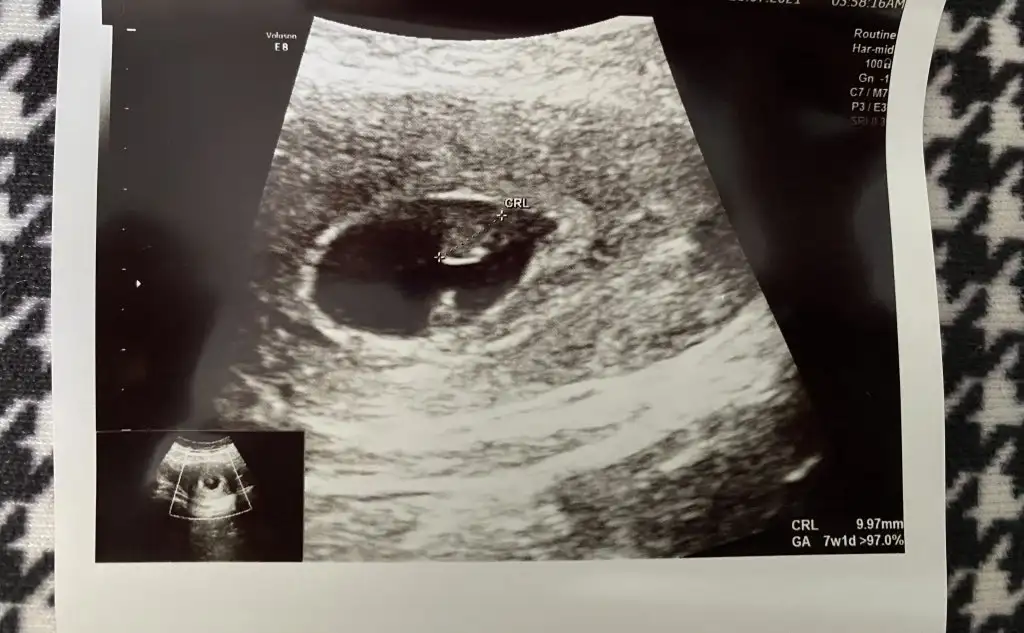

Erkek gibimerhaba :) ben de ekledim fotoğrafları. ilki 5 hafta, ikincisi 9 hafta. her ikisi de karından

Böyle bir bilgi bulmuştum bugünmerhaba :) ben de ekledim fotoğrafları. ilki 5 hafta, ikincisi 9 hafta. her ikisi de karından

Erkekvajinal ultrasonla bakıldı. 5 +5 haftalık.sizce cinsiyet ne